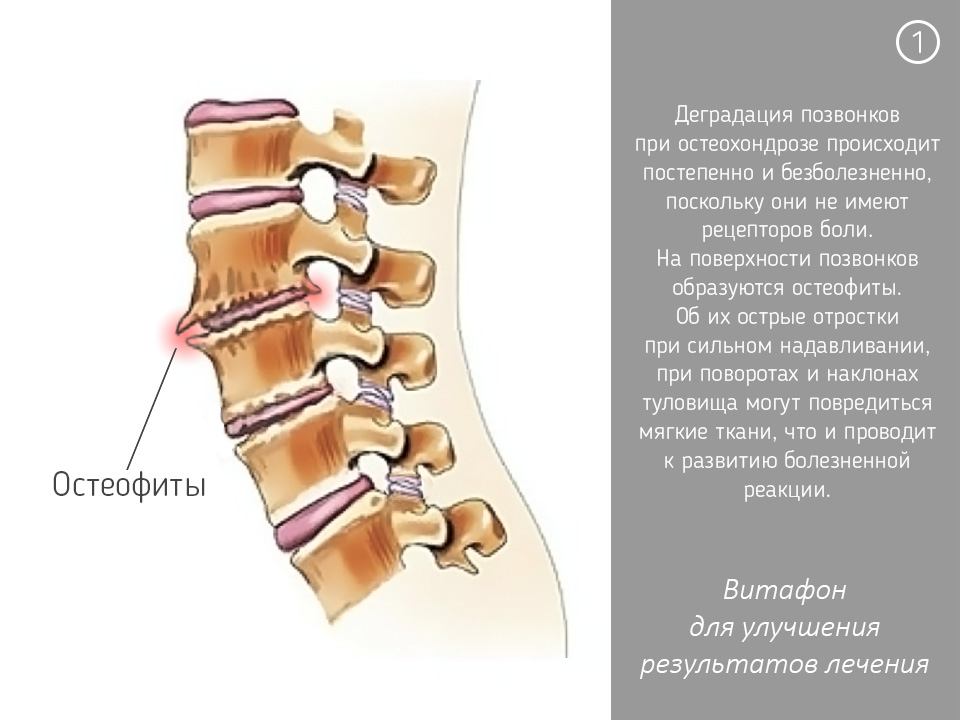

Остеоартрит фасеточных суставов: медицинские снимки и схемы